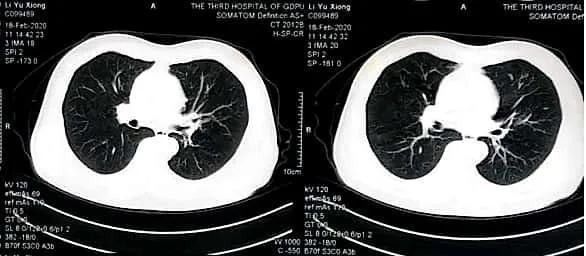

手术后CT

(与手术前CT的团状形肿瘤相对照,手术后CT肿瘤统一 位置消逝 了)